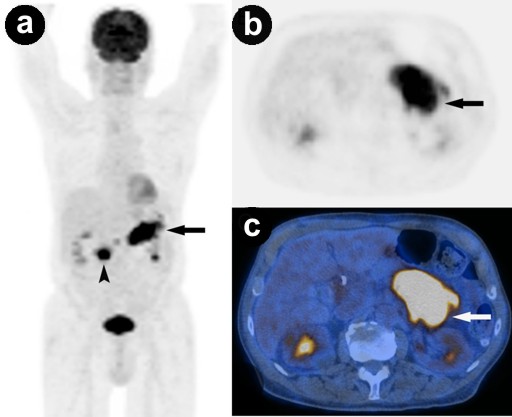

FDG-PET acquired on a combined PET-CT in-line system (Discovery VCT; GE HealthCare, Waukesha, WI, U.S.A.) showed an increased uptake by the intracystic solid tumor parts in the pancreatic head (standard uptake value, SUV: 15.4) and tail (SUV: 17.8), consistent with high metabolic activity (Figure 4).

Figure 4 a. Original attenuation-corrected coronal PET image demonstrates high uptake in the pancreatic head (arrowhead) and tail (arrow). b. c. Original attenuation-corrected axial PET image at the level of the pancreas shows high uptake in the pancreatic tail (arrow). Corresponding fused FDG-PET/CT at the same level. |

FDG-PET has proved to be useful for detecting malignant tumors of the pancreas, distant metastases in suspected pancreatic cancer, and parenchymal invasion of IPMN [13, 14]. Sperti et al. recently reported that 18F-FDG PET was more accurate than MRI and CT in distinguishing benign from malignant IPMNs [15]. Experience with intraductal oncocytic papillary neoplasm is limited, with only two case reports until now [4, 8]. Both cases showed strong FDG-uptake of the tumor nodules within the cystic components, with standard uptake values (SUVs) comparable to our case. Generally, benign tumors show significantly lower SUVs as compared to malignant tumors indicating a lower glucose-metabolism, which correlates with the diminished biological activity. The SUVs in the present case were very high. One reasonable explanation might be that intraductal oncocytic papillary neoplasms have high replication rates and therefore a higher glucose-metabolism. Oncocytomas have generally been proven to be notably active metabolically. As a matter of fact, several cases of non-pancreatic oncocytoma including those in the thyroid, pararenal, submandibular, and parotid glands showed intense activity on 18F-FDG-PET [16, 17, 18, 19]. In our case, the intraductal oncocytic papillary neoplasm was not solely intraepithelial since histological evaluation revealed multilocular transformation to invasive carcinoma which may have also caused high SUVs. However, in both published cases involving FDG-PET and intraductal oncocytic papillary neoplasms, there was no evidence of tumor invasion but there was still notable metabolic activity [4, 8].